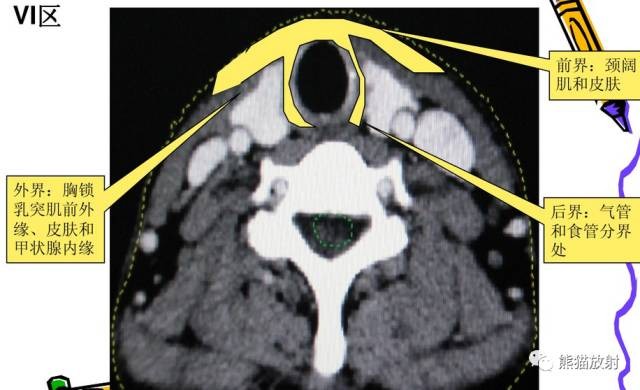

VI区:中央区淋巴结,包括喉前、气管前和气管旁淋巴结